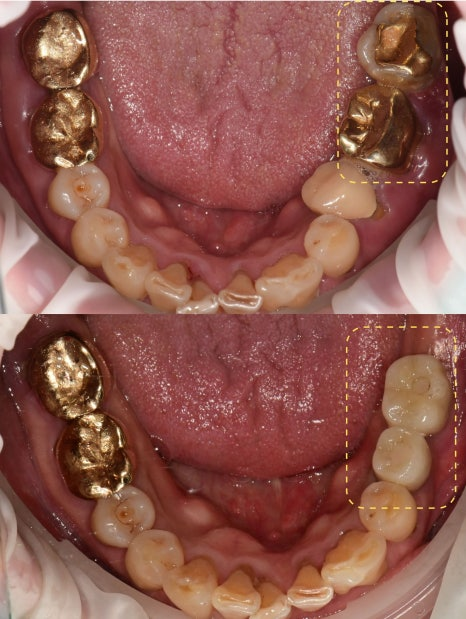

23.12.15 — 아래 임플란트 식립 / 24.09.04 — 치료 완료

위 회복 확인 후 아래를 순차적으로 진행했습니다. 빠르게 끝내는 것보다 각 단계마다 회복을 확인하며 진행하는 방식을 택했습니다. 총 치료기간은 약 1년 4개월이었습니다.

※ 전·후 사진은 동일인, 동일 장소, 동일 각도·조명 조건에서 촬영되었습니다.

23.04.25 (치료전)- 24.09.04 (치료후)